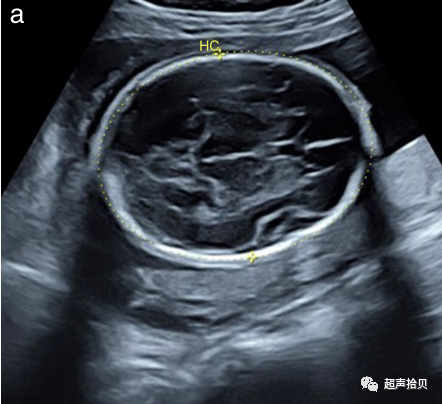

2. 应该获得一个图像来记录每个测量值。图1显示了适合于胎儿生物测量的静止图像示例;

图1标准胎儿生物测定法。超声测量:(a)头围(HC)、(b)腹围(AC)和(c)股骨长度(FL)。

头围(HC)

• HC既可以用椭圆法测量,也可以由BPD和OFD计算得出(良好的实践证据)

• 测量 HC 时,最好将游标从外到外放置推荐等级:C

2. -如果超声设备具有椭圆测量能力,则可以通过将椭圆放置在颅骨回声外缘来直接测量HC(图1a)。

3. -或者,HC可以从BPD和OFD中计算得出:如上文的“BPD”部分所述,使用前沿技术测量BPD,而OFD是通过将游标放置在额骨回声中点至和枕骨回声的中点的距离。然后将HC计算为HC=1.62×(BPD+OFD)。